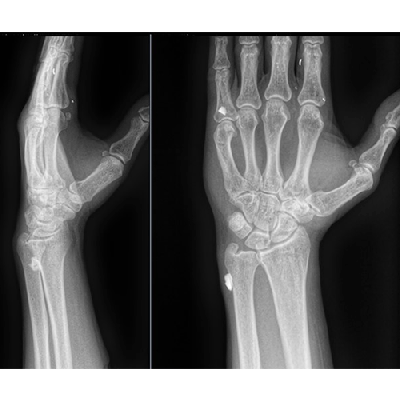

We are not a military hospital, but unfortunately, the number of wounded soldiers is currently so large that military medicine cannot cope with them and numerous civilian hospitals take over the treatment of wounded soldiers. Therefore, among ordinary civilian patients, we examine and treat wounded military personnel. In our hospital, these are mainly acubarotraumas, burns, gunshot wounds of the maxillofacial area, chest, abdominal organs, and of course most of all the trauma extremities.

From the first days we started to provide assistance to wounded civilians and the military from different parts of our country. Our work is to diagnose various injuries of the chest, abdomen, skull, pelvis and especially the limbs. We help thoracic, abdominal and facial surgeons, ophthalmologists, and especially orthopaedists in preoperative and postoperative stages of the treatment.

One of our tasks, as radiologists, has been to find foreign bodies in the people’s arms, legs, abdomen and thoracic wall with help of radiography or ultrasound. We also help in finding traumatic injuries to internal organs. Despite the lack of new equipment, we try to help all our patients as much as possible. Psychological support of patients is also important in our work, which I am doing.

Most examinations of the wounded are carried out in the wards due to the severity of the patients' condition, and X-rays are taken with the help of traditional non-digital machines. We are still waiting for the state CT scan in the hospital, we have only private near the hospital. The MRI machine (0.75 T) has been in use for more than 20 years. Among five stationary X-ray machines, only two are digital, and those without remote access to data for control, comparison. Of the eight ward X-ray machines, only one is digital. Our American colleagues presented it to our hospital. In some departments and operating theaters, there is no US equipment and C-arches for controlling operation procedures.